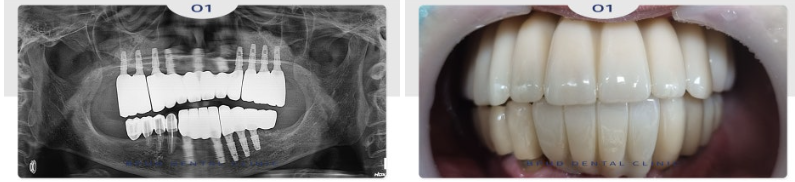

22.09.19

약 4~5개월 후 위쪽 임플란트도

식립을 진행하였습니다.

24.07.01

식립 4-5개월 후 최종 보철까지

완성하였는데요.

부평역치과 임플란트 수술 후

임시틀니를 장착해 드려

큰 문제 없이 마무리할 수 있었습니다.